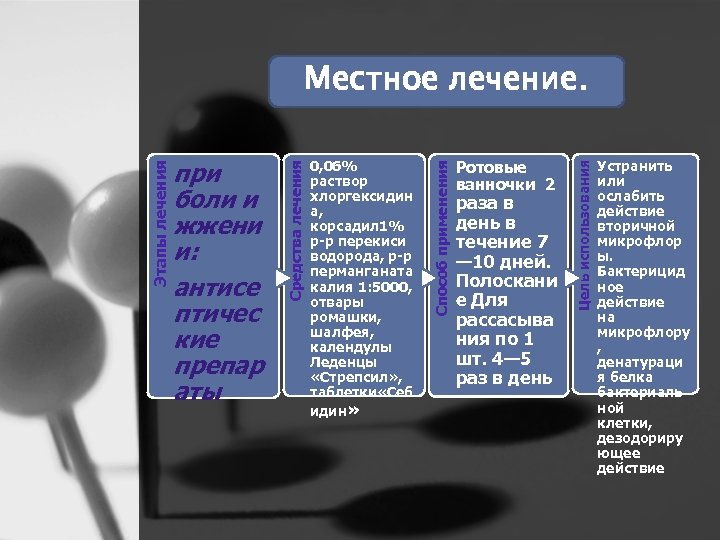

Ротовые ванночки 2 раза в день в течение 7 — 10 дней. Полоскани е Для рассасыва ния по 1 шт. 4— 5 раз в день Цель использования 0, 06% раствор хлоргексидин а, корсадил 1% р р перекиси водорода, р р перманганата калия 1: 5000, отвары ромашки, шалфея, календулы Леденцы «Стрепсил» , таблетки «Себ идин» Способ применения при боли и жжени и: антисе птичес кие препар аты Средства лечения Этапы лечения Местное лечение. Устранить или ослабить действие вторичной микрофлор ы. Бактерицид ное действие на микрофлору , денатураци я белка бактериаль ной клетки, дезодориру ющее действие